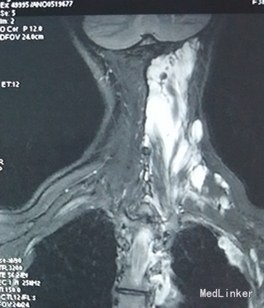

患者,女性,38岁“左侧头部闷痛伴左上肢麻木4天”入院。现病史:患者自诉于4天前无明显诱因出现左侧头部闷痛,伴左上肢麻木,左侧肩背部疼痛剧烈,左眼胀痛、耳鸣不适,无发热盗汗,无咳嗽咳痰,无头晕,无视物旋转等不适。当地医院颈部MRI报:1、颈部、咽后壁、左(L)胸部、纵膈内软组织大面积异常信号伴软组织肿块及骨质侵蚀,考虑恶性病变,2、双侧颈静脉链淋巴结增大,左(L)锁骨上淋巴结融合成团,3、颈椎曲度变直,键盘变性、膨隆。我院按“颈部包块”收治入院

查体:左侧颈部皮下饱满,触之稍韧,腹软无压痛,站立时左侧肩背部及左侧上腹部可扪及多个皮下包块,质软,无明显压痛,大小不一,大者约6*7cm,小者2*3cm,余无异常。 我院胸部CT: 1、左颈部、左背部及纵隔见大片软组织影,增强呈不均匀大小不等结片状强化,强化程度与血管强化程度相似,向上累及左咽旁间隙、左咽后间隙、左侧椎旁、椎后软组织,向前累及胸锁乳突肌后缘、左锁骨上,侵犯纵隔,以上纵隔为主,向后延伸椎旁、背部软组织及皮下脂肪间隙呈多发结节影,左侧胸膜呈多发结节影,向下侵犯左侧腹膜及左肾上极,呈多发大小不等软组织密度结节样改变,其内少许钙化影,所及多椎体及左侧肋骨多发骨质破坏;上述弥漫性病灶考虑肿瘤性病变,不除外血管瘤可能。 我院腹部CT: 1、左肾上区、脾周、腹膜后、左肾前、左侧腹腔及腹膜下多发团片状软组织密度影,散在多发钙化灶,左肾前肿块似与左肾静脉相通,左肾前肿块延左侧腰大肌前外侧向下延伸至盆腔左侧,左侧腹腔及腹膜下肿块向外播散至腹壁,腹直肌、腹外肌受侵,考虑肿瘤性病变,血管瘤不除外,建议进一步检查; 2.肝内多发低密度结节影,增强扫描呈渐进性强化,不除外血管瘤可能,建议必要时MR检查。

为求进一步诊断,来我科室之后行腹腔镜探查术和腹壁取活检术。确诊为多发性血管瘤。 侵及左侧咽喉部,左颈部、左背部及纵隔,左肾上区、脾周、腹膜后、左肾前、左侧腹腔及左侧腹壁